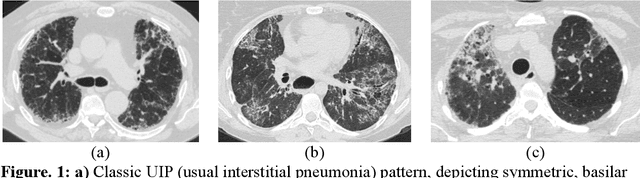

Abstract:Purpose: To utilize high-resolution quantitative CT (QCT) imaging features for prediction of diagnosis and prognosis in fibrosing interstitial lung diseases (ILD). Approach: 40 ILD patients (20 usual interstitial pneumonia (UIP), 20 non-UIP pattern ILD) were classified by expert consensus of 2 radiologists and followed for 7 years. Clinical variables were recorded. Following segmentation of the lung field, a total of 26 texture features were extracted using a lattice-based approach (TM model). The TM model was compared with previously histogram-based model (HM) for their abilities to classify UIP vs non-UIP. For prognostic assessment, survival analysis was performed comparing the expert diagnostic labels versus TM metrics. Results: In the classification analysis, the TM model outperformed the HM method with AUC of 0.70. While survival curves of UIP vs non-UIP expert labels in Cox regression analysis were not statistically different, TM QCT features allowed statistically significant partition of the cohort. Conclusions: TM model outperformed HM model in distinguishing UIP from non-UIP patterns. Most importantly, TM allows for partitioning of the cohort into distinct survival groups, whereas expert UIP vs non-UIP labeling does not. QCT TM models may improve diagnosis of ILD and offer more accurate prognostication, better guiding patient management.